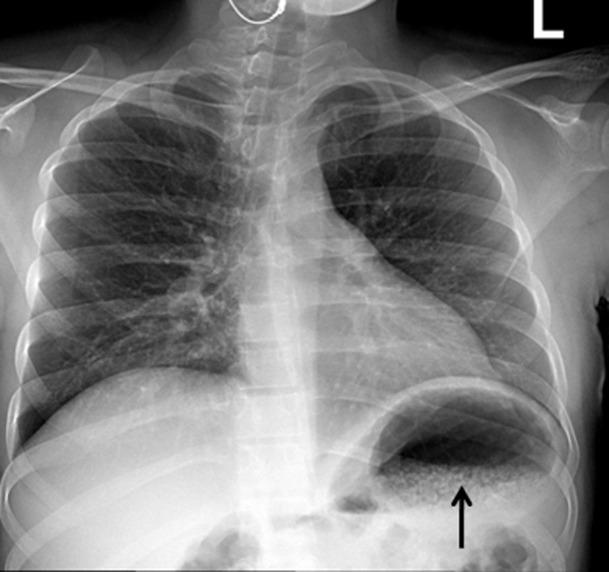

Emphysematous gastritis with portal venous air is a rare condition usually caused by gas forming organisms. This may be secondary to local spread of an infection through the mucosa or rarely hematogenous dissemination from a distant focus. We present a young diabetic woman with uncontrolled diabetes mellitus who was admitted with sepsis and severe abdominal symptoms. Investigation revealed emphysematous pyelonephritis due to E. coli infection associated with emphysematous gastritis and air in the portal tract. She improved with broad spectrum antibiotics, fluid resuscitation and electrolyte and diabetic management. To our knowledge this is the first report showing the association between emphysematous pyelonephritis and gastritis with air in the portal system.